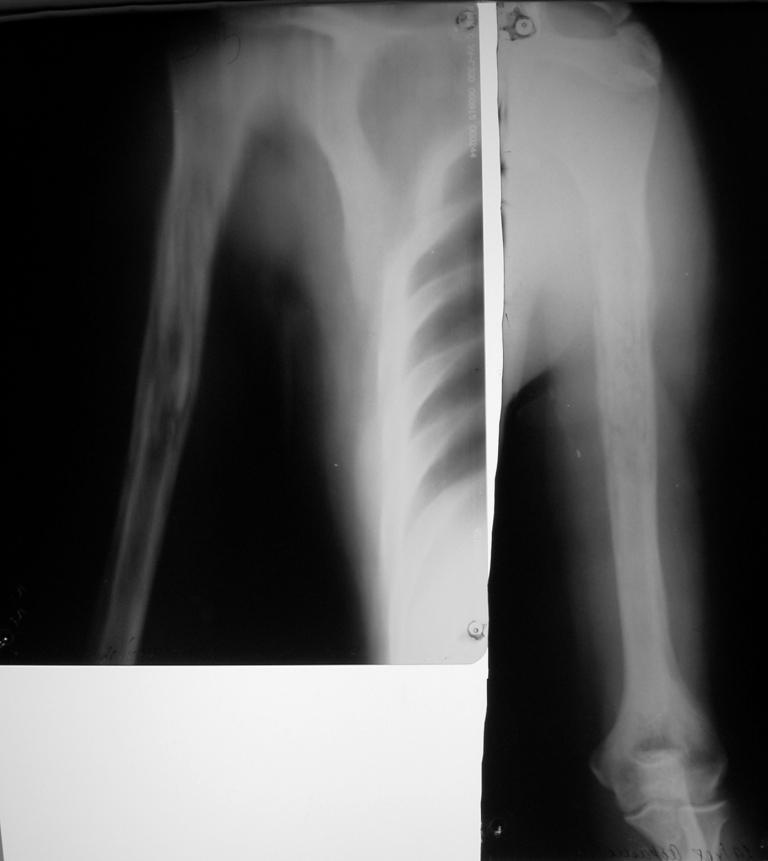

[Ortho] Остеомиелит плеча

К "гнойным хирургам" обратился больной 1982 г. р.

После ушиба мягких тканей в сентябре сего года и применения тепловых

процедур через 3 недели открылся свищ. Подскажите что делать? Может

быть римирование костномозгового канала ppcntv цемент с антибиотиком?